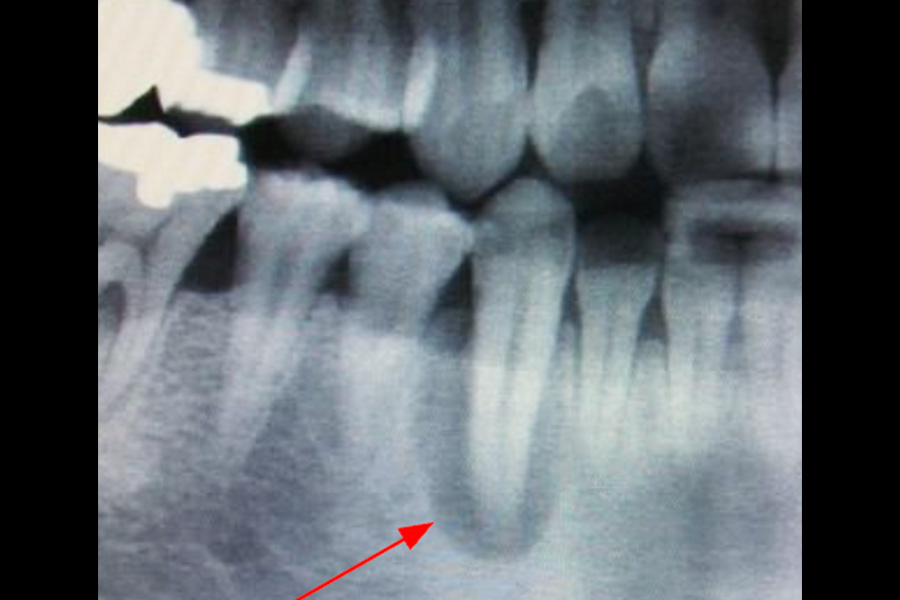

- スプリットクレスト(歯槽堤拡大術)

- 骨が細い為、骨造成が必要となる場合やインプラントの安定が得にくい可能性があるので、定期メンテナンスと自己ケアの両立が大切になります。